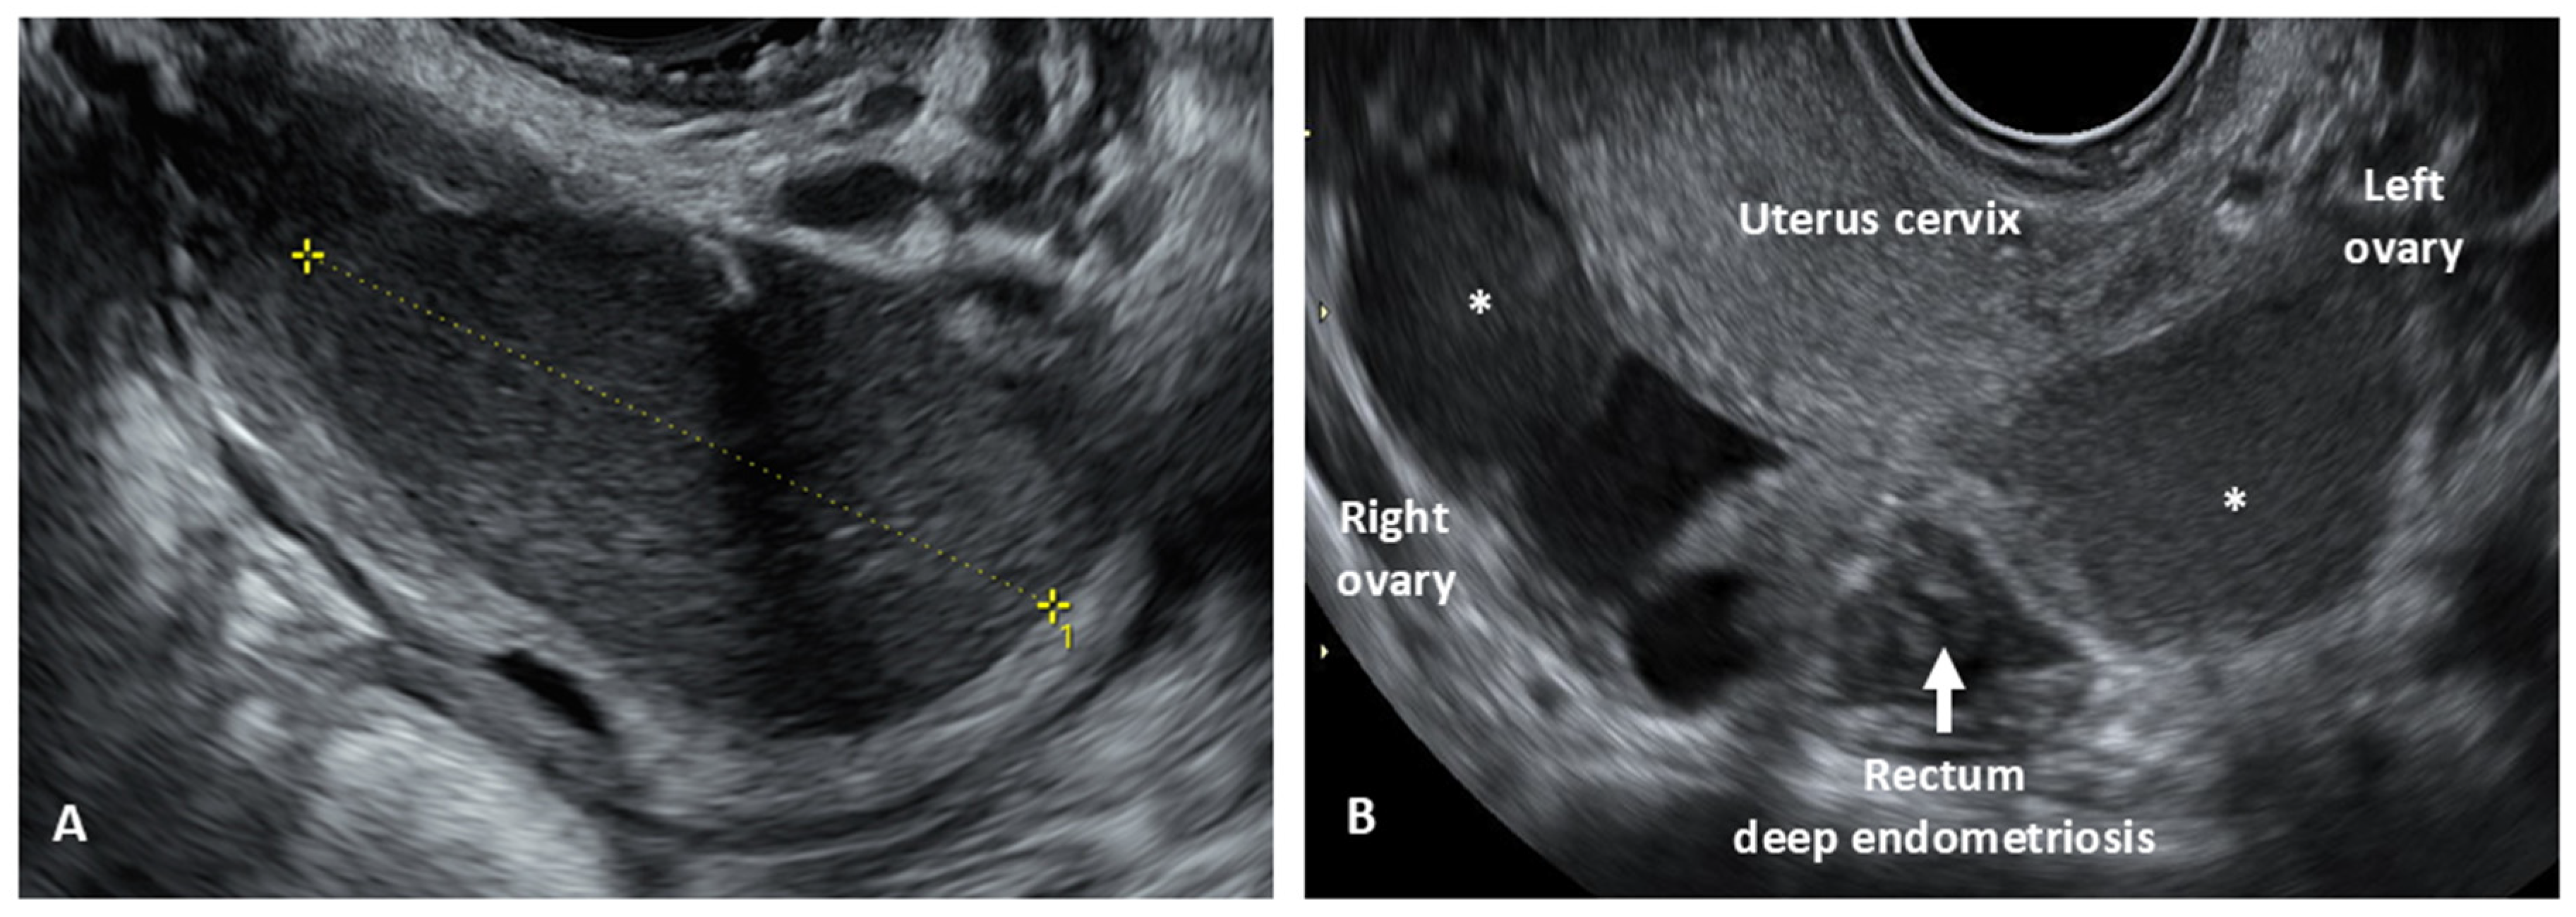

- Deep infiltrating endometriosis (DIE), defined as a lesion infiltrating the peritoneum and involving the retroperitoneal space or the walls of pelvic organs, larger than 5 mm.

- Goncalves, M.O.; Neto, J.S.; Andres, M.P.; Siufi, D.; de Mattos, L.A.; Abrao, M.S. Systematic evaluation of endometriosis by transvaginal ultrasound can accurately replace diagnostic laparoscopy, mainly for deep and ovarian endometriosis. Hum. Reprod. 2021, 36, 1492–1500. [Google Scholar] [CrossRef] [PubMed]

- Condous, G.; Gerges, B.; Thomassin-Naggara, I.; Becker, C.; Tomassetti, C.; Krentel, H.; van Herendael, B.J.; Malzoni, M.; Abrao, M.S.; Saridogan, E.; et al. Non-invasive imaging techniques for diagnosis of pelvic deep endometriosis and endometriosis classification systems: An International Consensus Statement. Ultrasound Obstet. Gynecol. 2024, 64, 129–144. [Google Scholar] [CrossRef]

- Guerriero, S.; Condous, G.; van den Bosch, T.; Valentin, L.; Leone, F.P.; Van Schoubroeck, D.; Exacoustos, C.; Installé, A.J.; Martins, W.P.; Abrao, M.S.; et al. Systematic approach to sonographic evaluation of the pelvis in women with suspected endometriosis, including terms, definitions and measurements: A consensus opinion from the International Deep Endo-metriosis Analysis (IDEA) group. Ultrasound Obstet. Gynecol. 2016, 48, 318–332. [Google Scholar] [CrossRef]

- Russo, C.; Lazzeri, L.; Siciliano, T.; Selntigia, A.; Farsetti, D.; Chiaramonte, C.; Martire, F.; Zupi, E.; Exacoustos, C. Reproducibility of #Enzian classification by transvaginal ultrasound and its correlation with symptoms. Facts Views Vis. Obgyn 2024, 16, 47–58. [Google Scholar] [CrossRef]